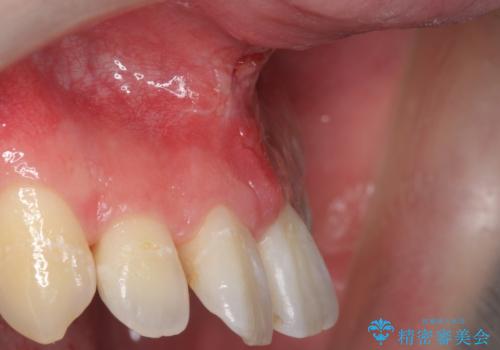

上唇小帯切除

担当医 青山卓弘